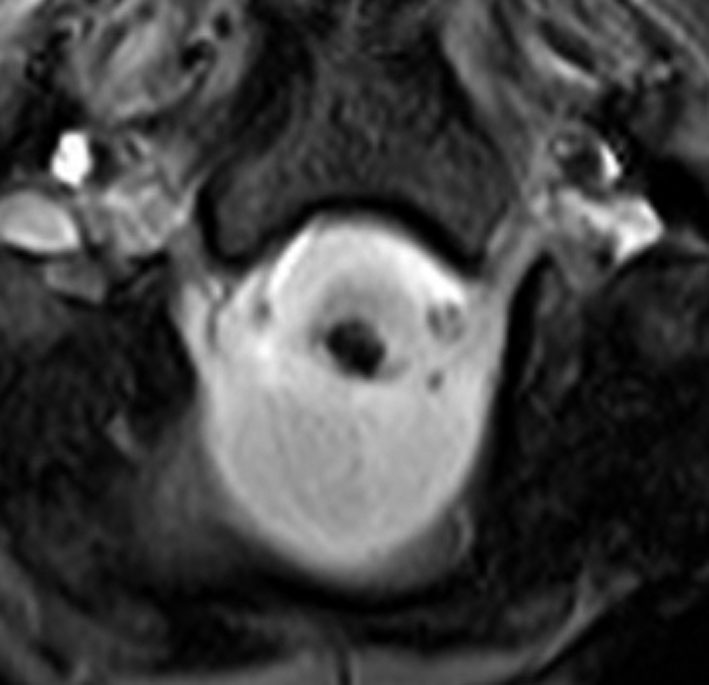

1歳5ヶ月で左小脳半球の髄芽腫になり手術と化学療法して,3歳になってから脳脊髄照射をしました。脳脊髄18グレイ,局所48グレイが入っています。18歳の学生の時のMRIで,左小脳萎縮がありますが普通の生活ができています。

18歳の時に突然,左上下肢の痺れと脱力が生じました。延髄下端から脊髄に小さな出血があります。様子を見ていたら症状はよくなりました。

その後数日の間に,小さな出血を繰り返して,嚥下障害,しゃっくり,頭痛,四肢のしびれなどが出ました。手術をしないで経過を見ました。

7年後のMRIです。延髄脊髄移行部(おそらくC1)に出血痕が残っています。放射線誘発海綿状血管腫といわれるものの画像所見ですが,ほんとのところは静脈閉塞によるうっ血症状と鬱血性の出血といわれています。

症状はすべて良くなりました。今は学校を卒業して,元気に働いています。